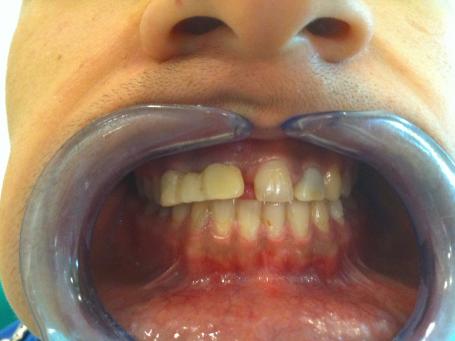

1°) Photo initiale

Patient âgé de 20 ans se présente au cabinet après une urgence dentaire avec une demande de réhabilitation esthétique. Suite à un accident (choc frontal) le patient s'est vu posé ce bridge provisoire en résine afonctionnel, inesthétique et non stable suite à l'urgence.